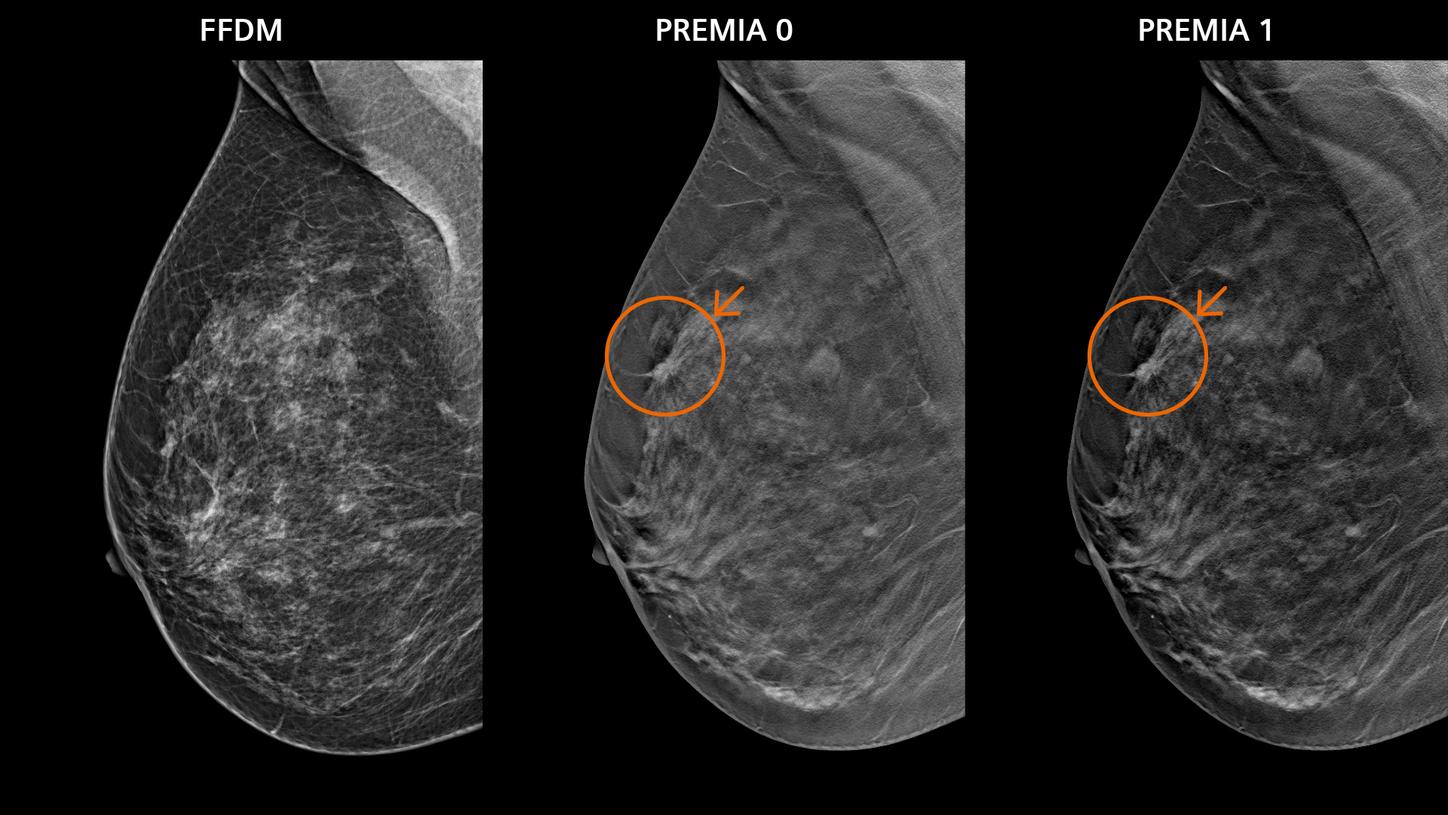

• PREMIA image reconstruction:

Improved image reconstruction framework

• Reduce artifacts and enhance visibility of calcifications and lesions